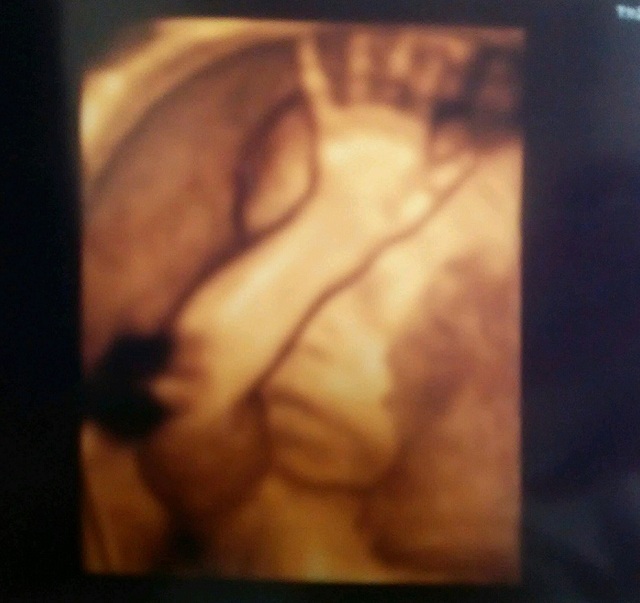

28週6日(28w6d・男の子)|megu51255 さん(27歳)

エコー写真撮影時のエピソード:

4Dのエコー写真でこんなに、はっきりと輪郭や鼻、口、手が見えたのがとてもうれしくて感動した。旦那さんもうれしくて泣きそうになっていた。

旦那さんとエコー写真を見て鼻は私で口は旦那さんに似てるね!なんて話をして赤ちゃんがお腹にいるんだと実感出来た。実際に生まれると写真の通りで笑ってしまった。